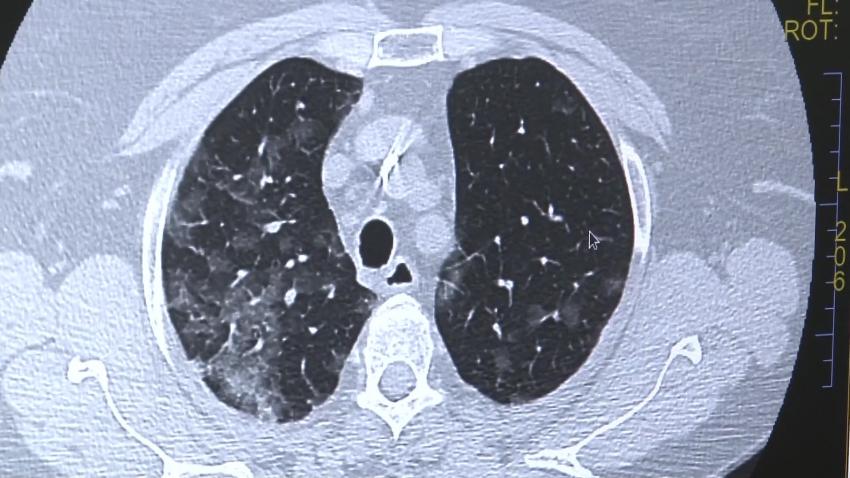

“Pacientul sau medicul acestuia pot să introducă în platformă imagini CT,istoricul medical, informații despre alte afecțiuni dar pot să adauge și probele funcționale pe care le-a făcut pacientul de-a lungul timpului, de exemplu, analiza de spirometrie. Odată finalizată această etapă, informațiile întră în atenția echipei de specialiști ai spitalului nostru care evaluează cazul. În unele situații sunt solicitate informații sau investigații suplimentare, după care echipa noastră se pronunță asupra diagnosticului, practic realizează o încadrare în boală. Opinia medicală a echipei de pneumologi și radiologi vine însoțită de recomandări de investigații și monitorizare. Nu oferim însă tratament”, spune SL. Dr Diana Manolescu, director medical Spitalul de Boli Infecțioase și Pneumoftiziologie Dr. Victor Babeș Timișoara.

“Pneumonia Interstițială Difuza( PID) reprezintă un grup de peste 200 de afecțiuni respiratorii care afectează structura anatomică a plămânului. Diagnosticarea este dificila din cauza suprapunerii numărului mare de boli care au aceleași simptome. De aceea, diferență o face experiență medicală îndeosebi în ceea ce privește partea imagistică. Din păcate, unele dintre afecțiuni sunt foarte severe si au o cu o rată de supravițuire medie de 4-5 ani”, spune SL. Dr Diana Manolescu, director medical Spitalul de Boli Infecțioase și Pneumoftiziologie Dr. Victor Babeș Timișoara.